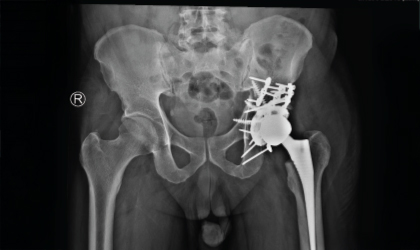

Complex Hip, Restored

This 62 year old man had a fracture dislocation of his hip following a road traffic accident.